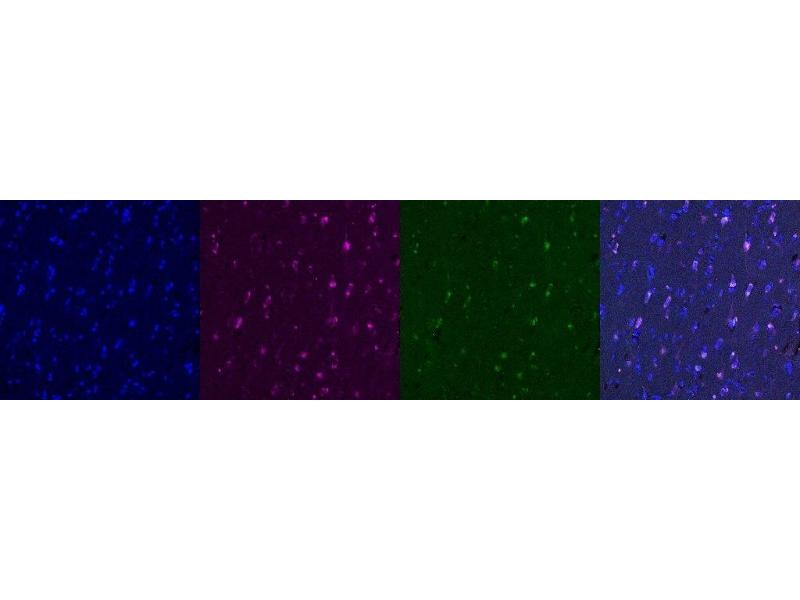

Dieser Maus Monoklonal Antikörper detektiert spezifisch Interferon gamma in IHC. Es zeigt Reaktivität gegenüber Proben von Human.

Immunohistochemistry (IHC)